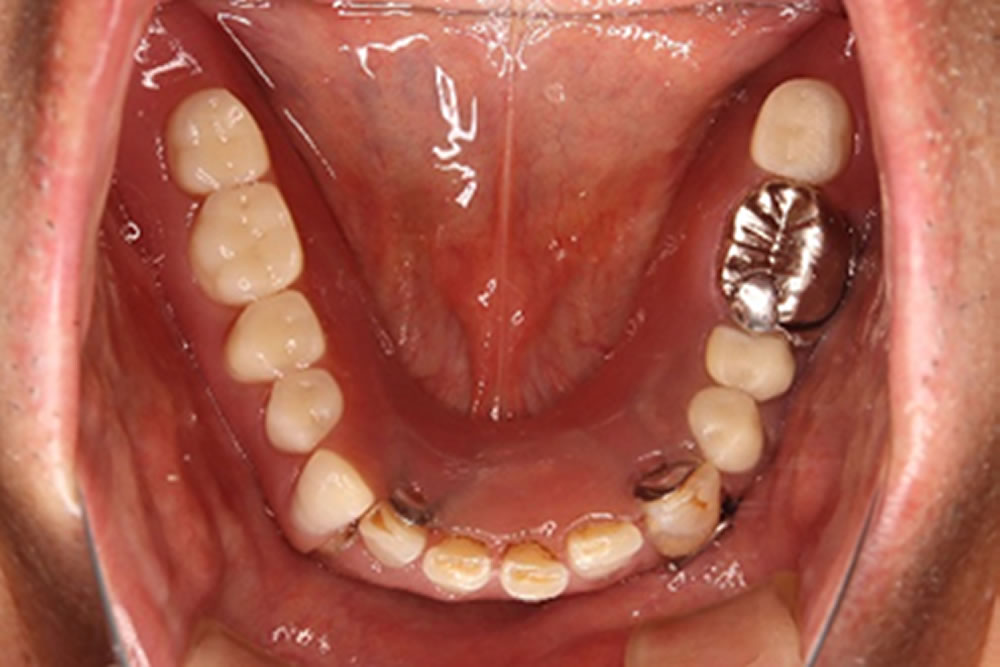

治療前の状態と患者さんの希望

上下顎とも虫歯や歯根破折などで、治療した冠が外れたり、歯が抜けたままになったりしていて、上下の歯がかみ合うところが、ほとんどありませんでした。

上顎前歯も、ほんのわずかの歯根が歯肉の中に残っているだけの状態で、見た目が悪いため、患者さんは歯が見えないように、口を開けないように話をされていました。精密検査をして、虫歯治療や歯周病治療を行って残せる歯は残し、上下の義歯治療を行うことにしました。